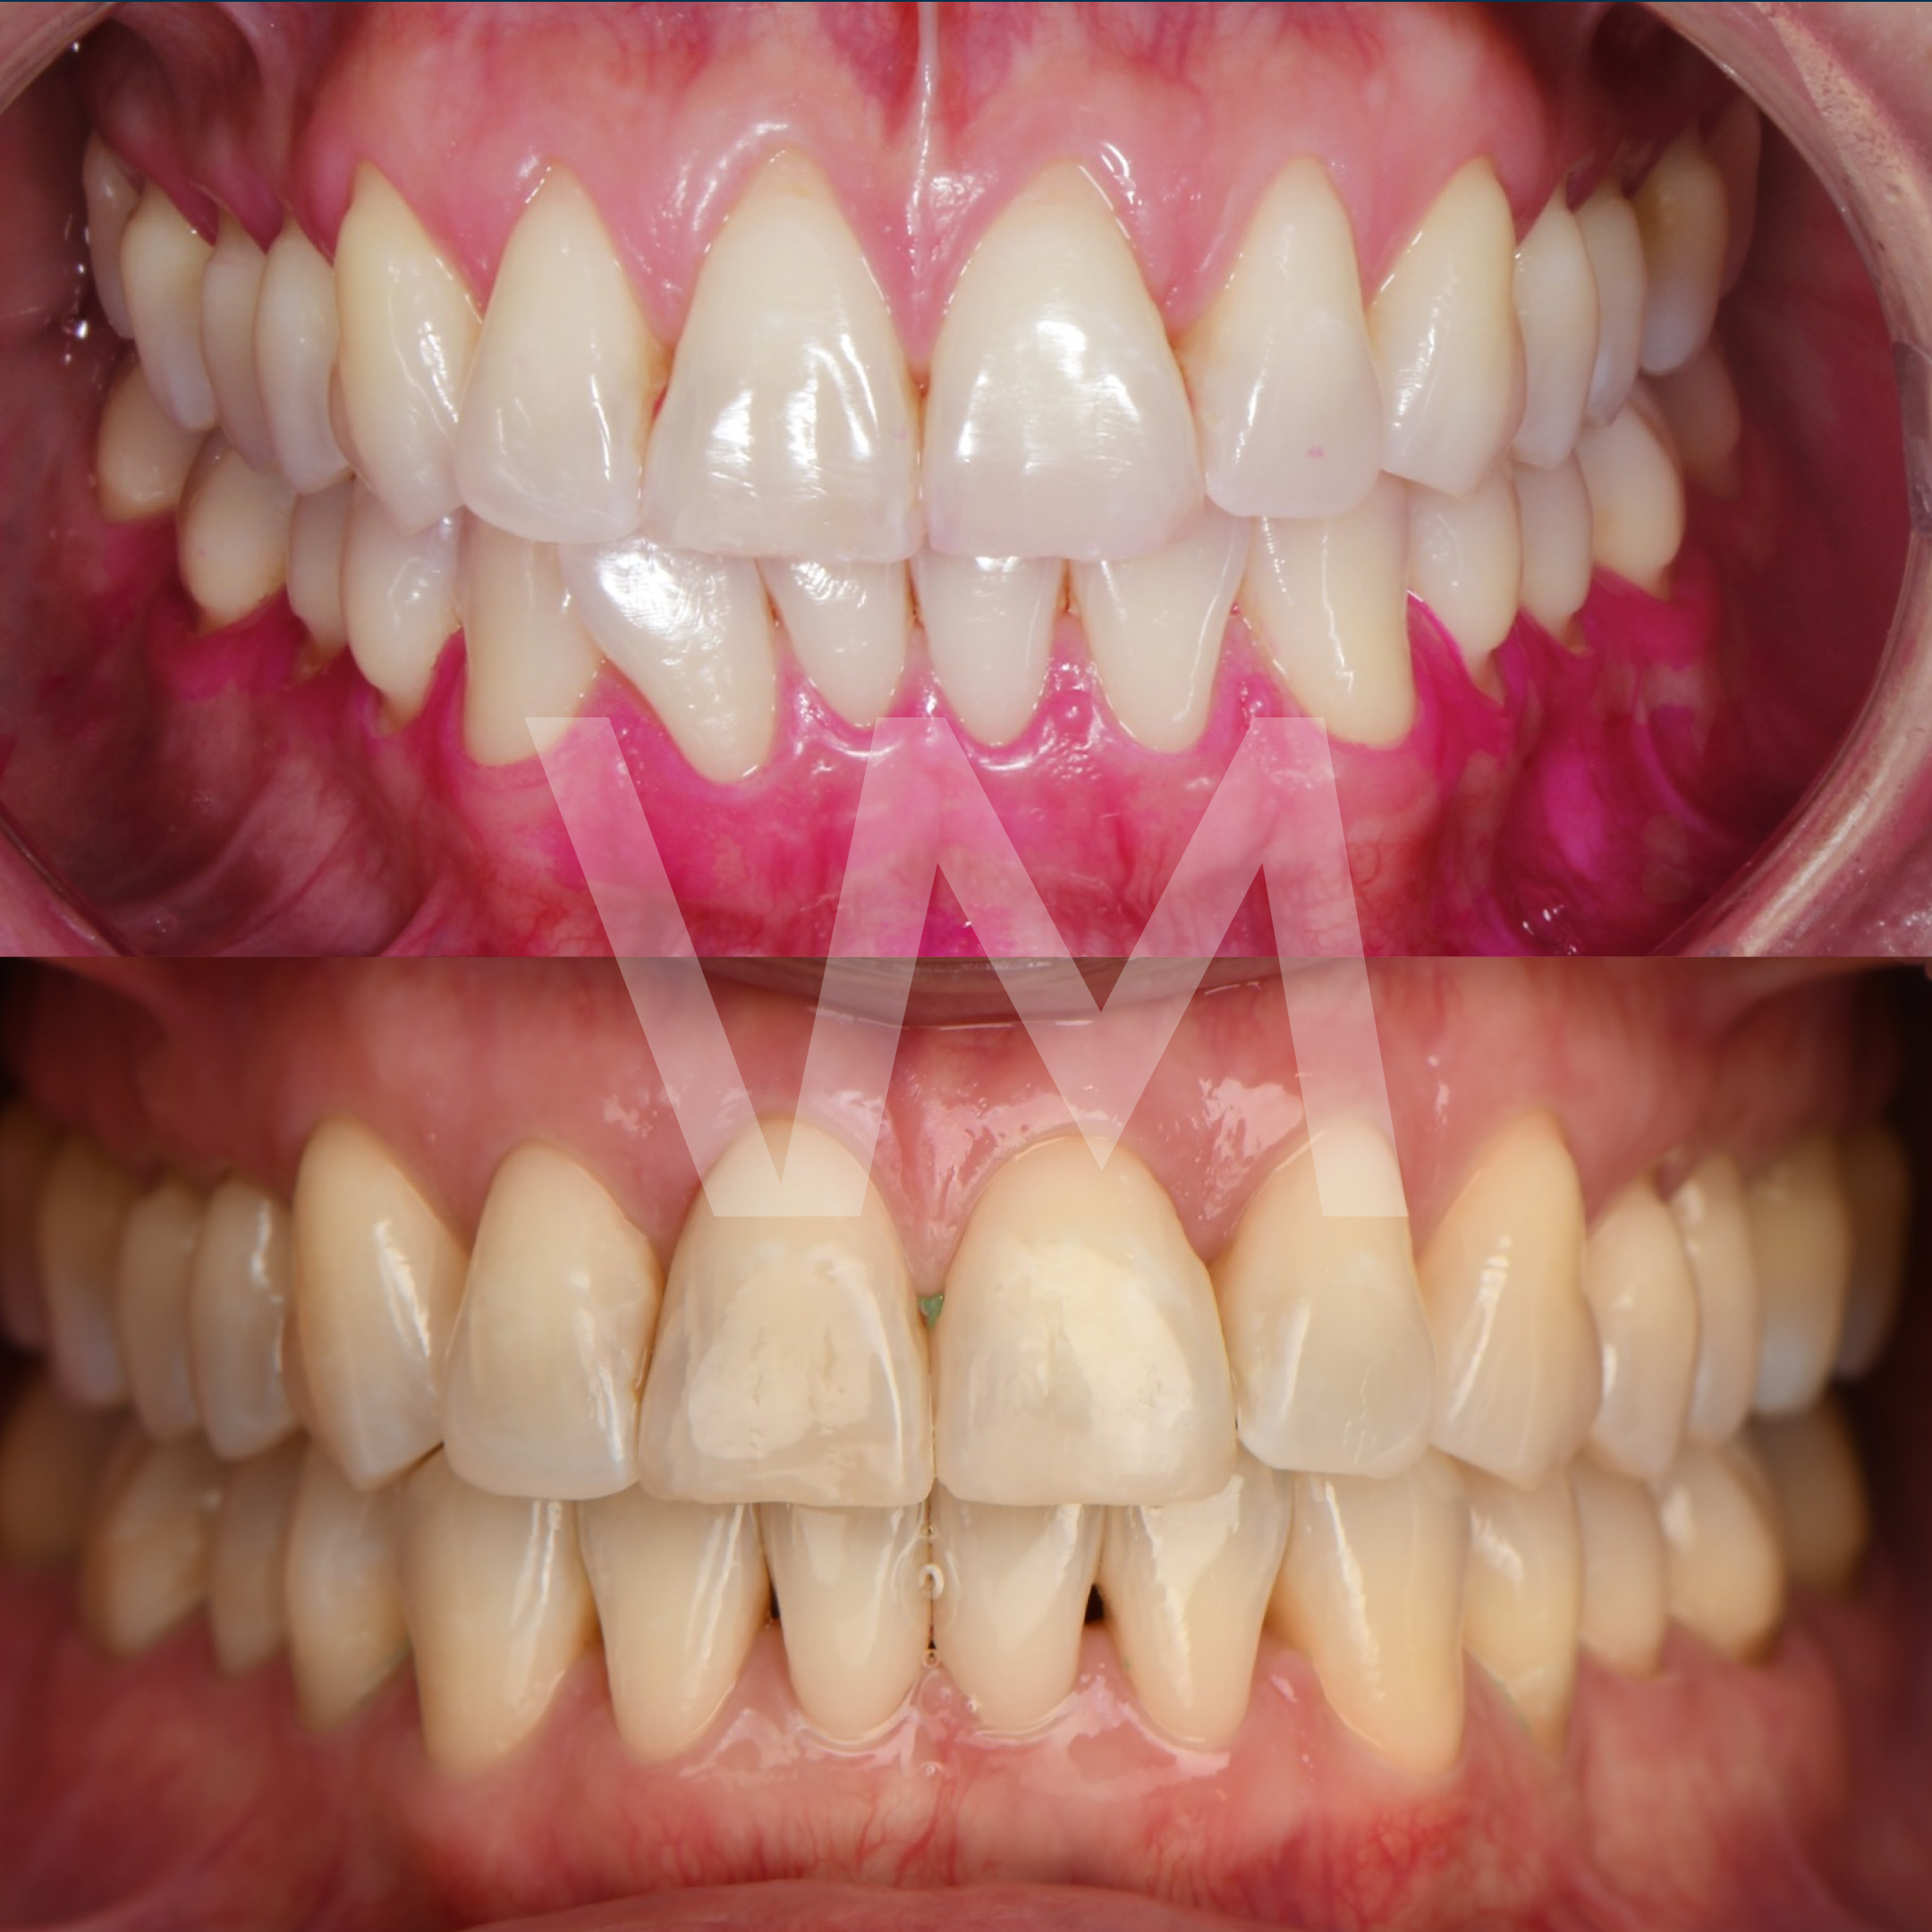

Cirugías de Injertos de Encía del Paladar e Injertos Sintéticos para el Tratamiento de Recesiones Gingivales

Las recesiones gingivales son un problema común en el que las encías retroceden, dejando expuesta la raíz del diente y aumentando el riesgo de sensibilidad dental, deterioro del hueso y pérdida de dientes. Para corregir estas recesiones y restaurar la salud gingival, se pueden realizar cirugías de injertos de encía del paladar e injertos sintéticos.

Casos clínicos realizados por la Dra. Paulina